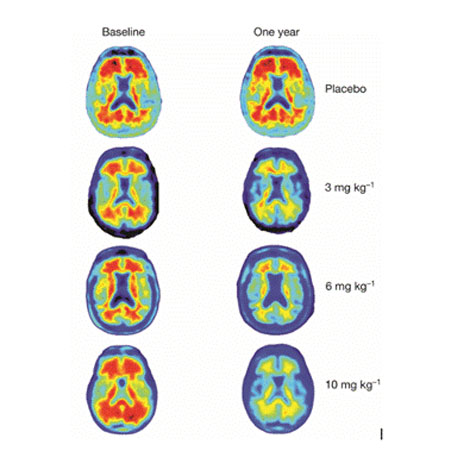

Các nhà khoa học thông báo họ hết sức bất ngờ khi nhìn thấy ở những vị trí bệnh nhân Alzheimer được chữa trị với liều cao kháng thể Aducanumab đã hoàn toàn không còn mảng bám amyloid ngăn chặn các tế bào não giao tiếp với nhau - nguyên nhân dẫn đến sự mất trí nhớ không thể phục hồi và suy giảm khả năng nhận thức.

| Những mảng bám amyloid (trái) được tống khứ sạch sau khi dùng thuốc Aducanumab (phải). |

David Allsop, Giáo sư khoa thần kinh học Đại học Lancaster (Anh) đánh giá, phát hiện này là bước đột phá trong điều trị bệnh Alzheimer. Giáo sư Roger Nitsch ở Viện Y khoa Tái sinh thuộc Đại học Zurich (Thụy Sĩ) bình luận: "Kết quả từ cuộc thử nghiệm lâm sàng đầu tiên này cho phép chúng ta lạc quan hơn về liệu pháp điều trị bệnh Alzheimer. Nơi nhóm bệnh nhân được thử nghiệm với liều cao Aducanumab, mảng bám amyloid biến mất hoàn toàn. Điều đó cho thấy hiệu quả của thuốc là chưa từng có.